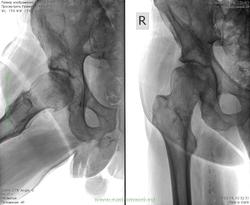

Мужчина 56 лет. Правый тазобедренный сустав. Беспокоят умеренные боли 2-3 месяца.

Коксартроз III ст.

Я первый скажу это страшное (для Великого и Ужасного, КТ корифея нашего) - асептический некроз головки бедра. По снимку заключил, надеюсь, не один только я.

Некоторых и по рукам били. Прямая проекция не ах... ДОА, стадию сами выберите.

Дефартроз стадия 3 по Косинской , с некрозом асептическим да и атеросклероз имеется

Не хочется обять бузу разводить, но с асептическим некрозом не согласна. Есть неравномерный остеосклероз голвки с кистовидными просветлениями, так же как и теле подвздошной кости, а это признаки артроза III ст. Ну и ещё, если быть совсем уж скурпулёзным, следует отметить хонроматоз сустава.

Почему же мне импрессионные переломы в головке мерещатся?

Обзорный снимок таза дал бы больше информации. Как версия - рак предстательной железы с метастазами в кости таза и бедра.

Спасибо всем за мнения. Я, когда описывал, написал остеоартроз II ст. с признаками аваскулярного некроза.